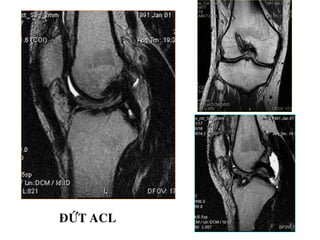

TOÅN THÖÔNG DAÂY CHAÈNG CHEÙO

- Daây chaèng coù höôùng ñi baát thöôøng, maát lieân tuïc moät

phaàn, coù tín hieäu dòch cao treân T2W beân trong, daây

chaèng phuø daøy leân (toån thöông caáp) hay khoâng daøy (toån

thöông maïn).

- Maát lieân tuïc hoaøn toaøn, khoâng thaáy daây chaèng treân

phim.

Toån thöông caáp ACL

Ñöùt ACL

Toån thöông maïn ACL

ĐỨT HOAØN TOAØN ACL